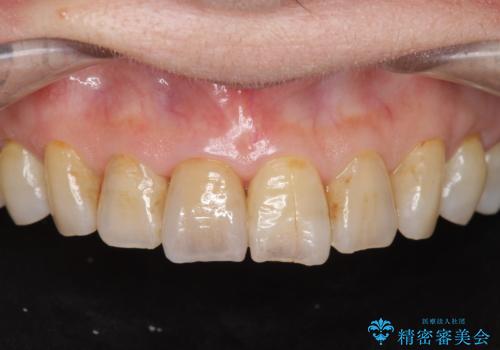

当法人でご提案できる最上位クラスのジルコニアクラウンです。

透明感や周囲の歯との色の調和に大変ご満足いただけました。